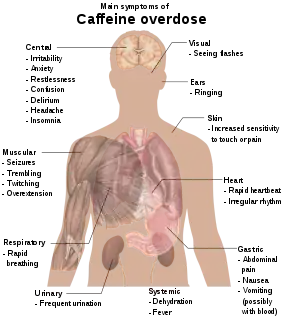

Consumption of 1–1.5 grams (1,000–1,500 mg) per day is associated with a condition known as caffeinism.[138] Caffeinism usually combines caffeine dependency with a wide range of unpleasant symptoms including nervousness, irritability, restlessness, insomnia, headaches, and palpitations after caffeine use.[139]

Caffeine overdose can result in a state of central nervous system overstimulation known as caffeine intoxication, a clinically significant temporary condition that develops during, or shortly after, the consumption of caffeine.[140] This syndrome typically occurs only after ingestion of large amounts of caffeine, well over the amounts found in typical caffeinated beverages and caffeine tablets (e.g., more than 400–500 mg at a time). According to the DSM-5, caffeine intoxication may be diagnosed if five (or more) of the following symptoms develop after recent consumption of caffeine: restlessness, nervousness, excitement, insomnia, flushed face, diuresis, gastrointestinal disturbance, muscle twitching, rambling flow of thought and speech, tachycardia or cardiac arrhythmia, periods of inexhaustibility, and psychomotor agitation.[141]

According to the International Classification of Diseases (ICD-11), cases of very high caffeine intake (e.g. > 5 g) may result in caffeine intoxication with symptoms including mania, depression, lapses in judgment, disorientation, disinhibition, delusions, hallucinations or psychosis, and rhabdomyolysis.[140]